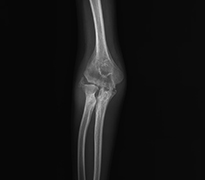

Dirsek Kireçlenmesi